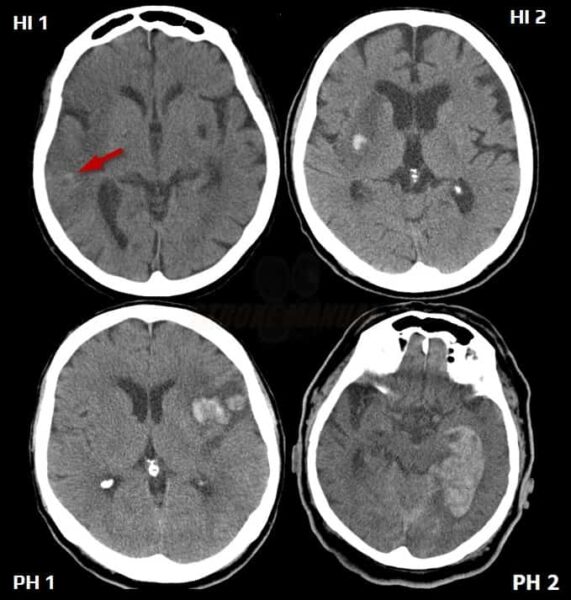

No significant differences were observed between the OCR and RTX treatment groups at 2, 4, and more than 4 years, although both groups showed a progressive accumulation of immune marker deficiencies over time (Figure 1). By year 4 of treatment, deficiencies were most common in IgM (26-31%), followed by IgG (12-13%), IgA (4-7%), lymphocytes (5.3-5.4%), and neutrophils (0-1.7%).

Screen shot 2025 05 06 at 8.17.56 pm Noun slideshow grey Screen shot 2025 05 06 at 8.18.17 pm Screen shot 2025 05 06 at 8.18.33 pm

Figure 1. Prevalence of immune marker deficiencies across treatment duration.

Bar charts showing the percentage of OCR- versus RTX-treated patients developing new immunoglobulin and cell count deficiencies at three time points (2, 4, and >4 years of treatment).

Survival analysis reveals that RTX is associated with significantly higher risks of developing IgM deficiency (HR=1.6, p=0.016, 95% CI 1.09-2.34) and IgA deficiency (HR=2.38, p=0.048, 95% CI 1.01-5.63) compared to OCR, despite similar cross-sectional prevalence rates. Linear regression analysis confirms RTX causes significantly faster IgM depletion (p=0.0044 for slope difference, p < 0.05 in mixed model, Figure 2).

Igm trajectories Noun slideshow grey Igg trajectories Iga trajectories Neutrophil trajectories Lymphocyte trajectories All parameters survival curves

Figure 2.  Longitudinal immune marker trajectories by treatment regimen

Spaghetti plots show individual patient data (thin lines) and demonstrate considerable inter-patient variability. Treatment-specific regression lines (thick lines, with shading that demonstrates 95% CI) show overall trends. Deficiency threshold is represented by red dotted lines. Kaplan-Meier curves depict survival analysis.